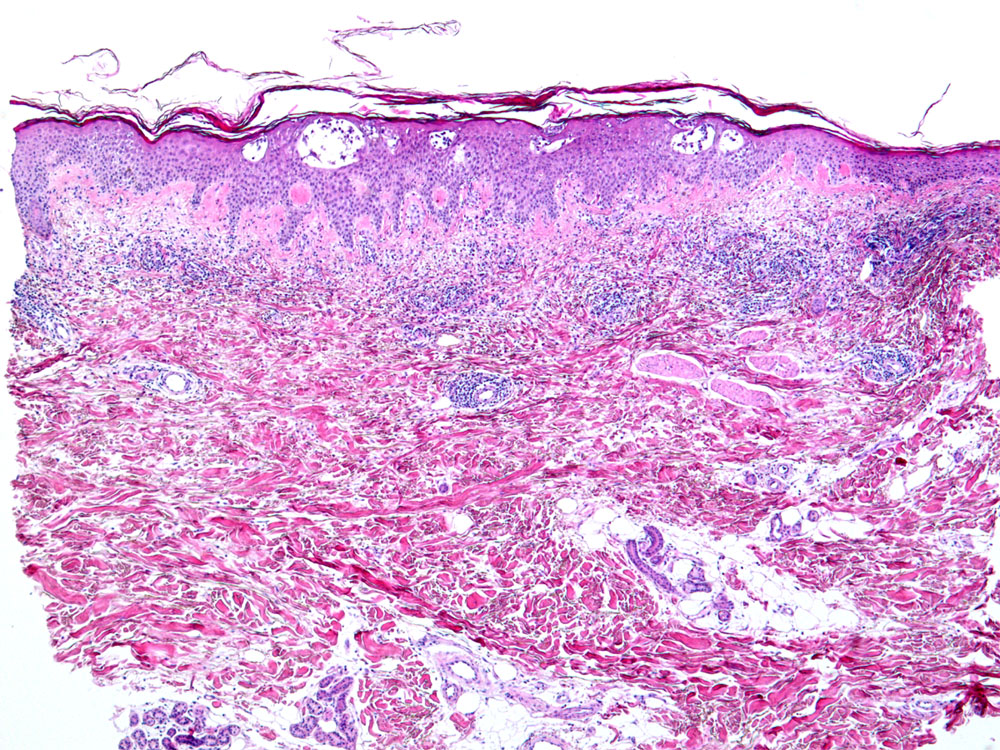

Entzündliche Hautreaktion mit Spongiose. Die Spongiose ist definiert als interzelluläres Ödem von Epidermis und/oder Adnexepithel, erkennbar an der Verbreiterung der Interzellularräume im Epithel. Bei gering ausgeprägter Spongiose stehen benachbarte Keratinozyten über verlängerte Interzellularbrücken noch miteinander in Kontakt, während bei stärkerer Ausprägung die desmosomalen Verbindungen dem Ödem nicht mehr standhalten und rupturieren, so dass sich die Zellen voneinander lösen und ein intraepitheliales Bläschen (spongiotisches Bläschen) entsteht. Dieser Prozess ist Ausdruck einer Entzündungsreaktion, die in der Regel durch Lymphozyten, seltener durch eosinophile oder neutrophile Granulozyten vermittelt wird. Die beteiligten Zellen sind im betroffenen Epithel (lymphozytäre Exozytose) und in der oberen Dermis nachweisbar. Verteilungsmuster und Zusammensetzung der Entzündungszellen können einen Hinweis geben auf die Ursache des spongiotischen Reaktionsmusters. Man unterscheidet klinisch und histopathologisch unterschiedliche Stadien (akut-subakut-chronisch).

Histologisch zeigen akute Ekzeme eine ausgeprägte Spongiose mit intraepithelialer Bläschenbildung, eine Parakeratose und Krustenauflagerungen, im chronischen Stadium eine Verminderung der Spongiose, eine Akanthose und Hyperparakeratose. Bei alten Läsionen können Parakeratosehügel und eine Epidermishyperplasie der einzige Hinweis auf eine spongiotische Dermatitis sein. Die Epidermishyperplasie ist teilweise eine Folge des chronischen Reibens und Kratzens der juckenden Haut. Das Entzündungsinfiltrat in der oberen Dermis besteht aus Lymphozyten und Histiozyten, zum Teil auch aus neutrophilen und eosinophilen Granulozyten. In der Epidermis dominieren Lymphozyten (lymphozytäre Exozytose). Akute, subakute und chronische Veränderungen können beim gleichen Patienten nebeneinander vorkommen.

Morphologische Merkmale:

• Verdickte Epidermis (Akanthose)

• Spongiose (interzelluläres Ödem der Epidermis)

• Spongiotische Vesikel (intraepitheliale Bläschenbildung)

• Parakeratotische Verhornung (Verhornte Zellen mit erkennbaren Zellkernen)

• Ödem der papillären Dermis (Aufhellung)

• Oberflächlich dermales perivaskulär betontes Entzündungsinfiltrat

• Lymphozyten, Histiozyten, neutrophile und eosinophile Granulozyten